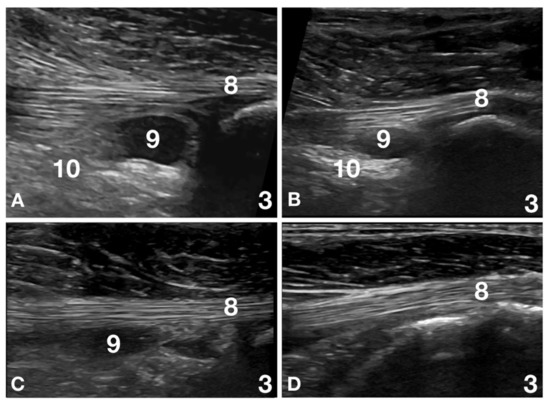

2.3. Ultrasound Evaluation